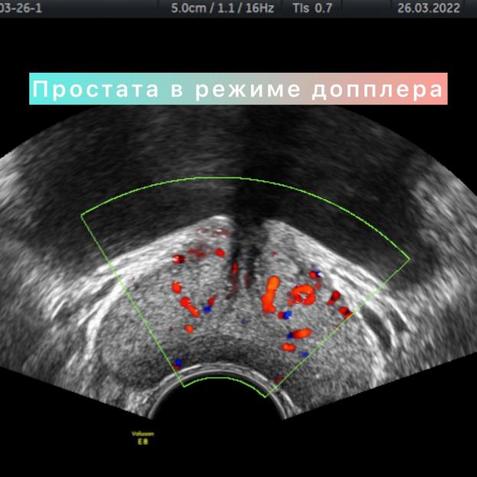

УЗИ предстательной железы возможно проводить двумя методами: датчиком через переднюю брюшную стенку (трансабдоминально) и датчиком через прямую кишку (трансректально) - ТРУЗИ.

В результате УЗИ-осмотра через прямую кишку информации гораздо больше. Возможна визуализация зон предстательной железы, подробное изучение простатического отдела уретры, состояние семенных пузырьков, визуализация мелких кист или участков фиброза, очаговых образований малых размеров.